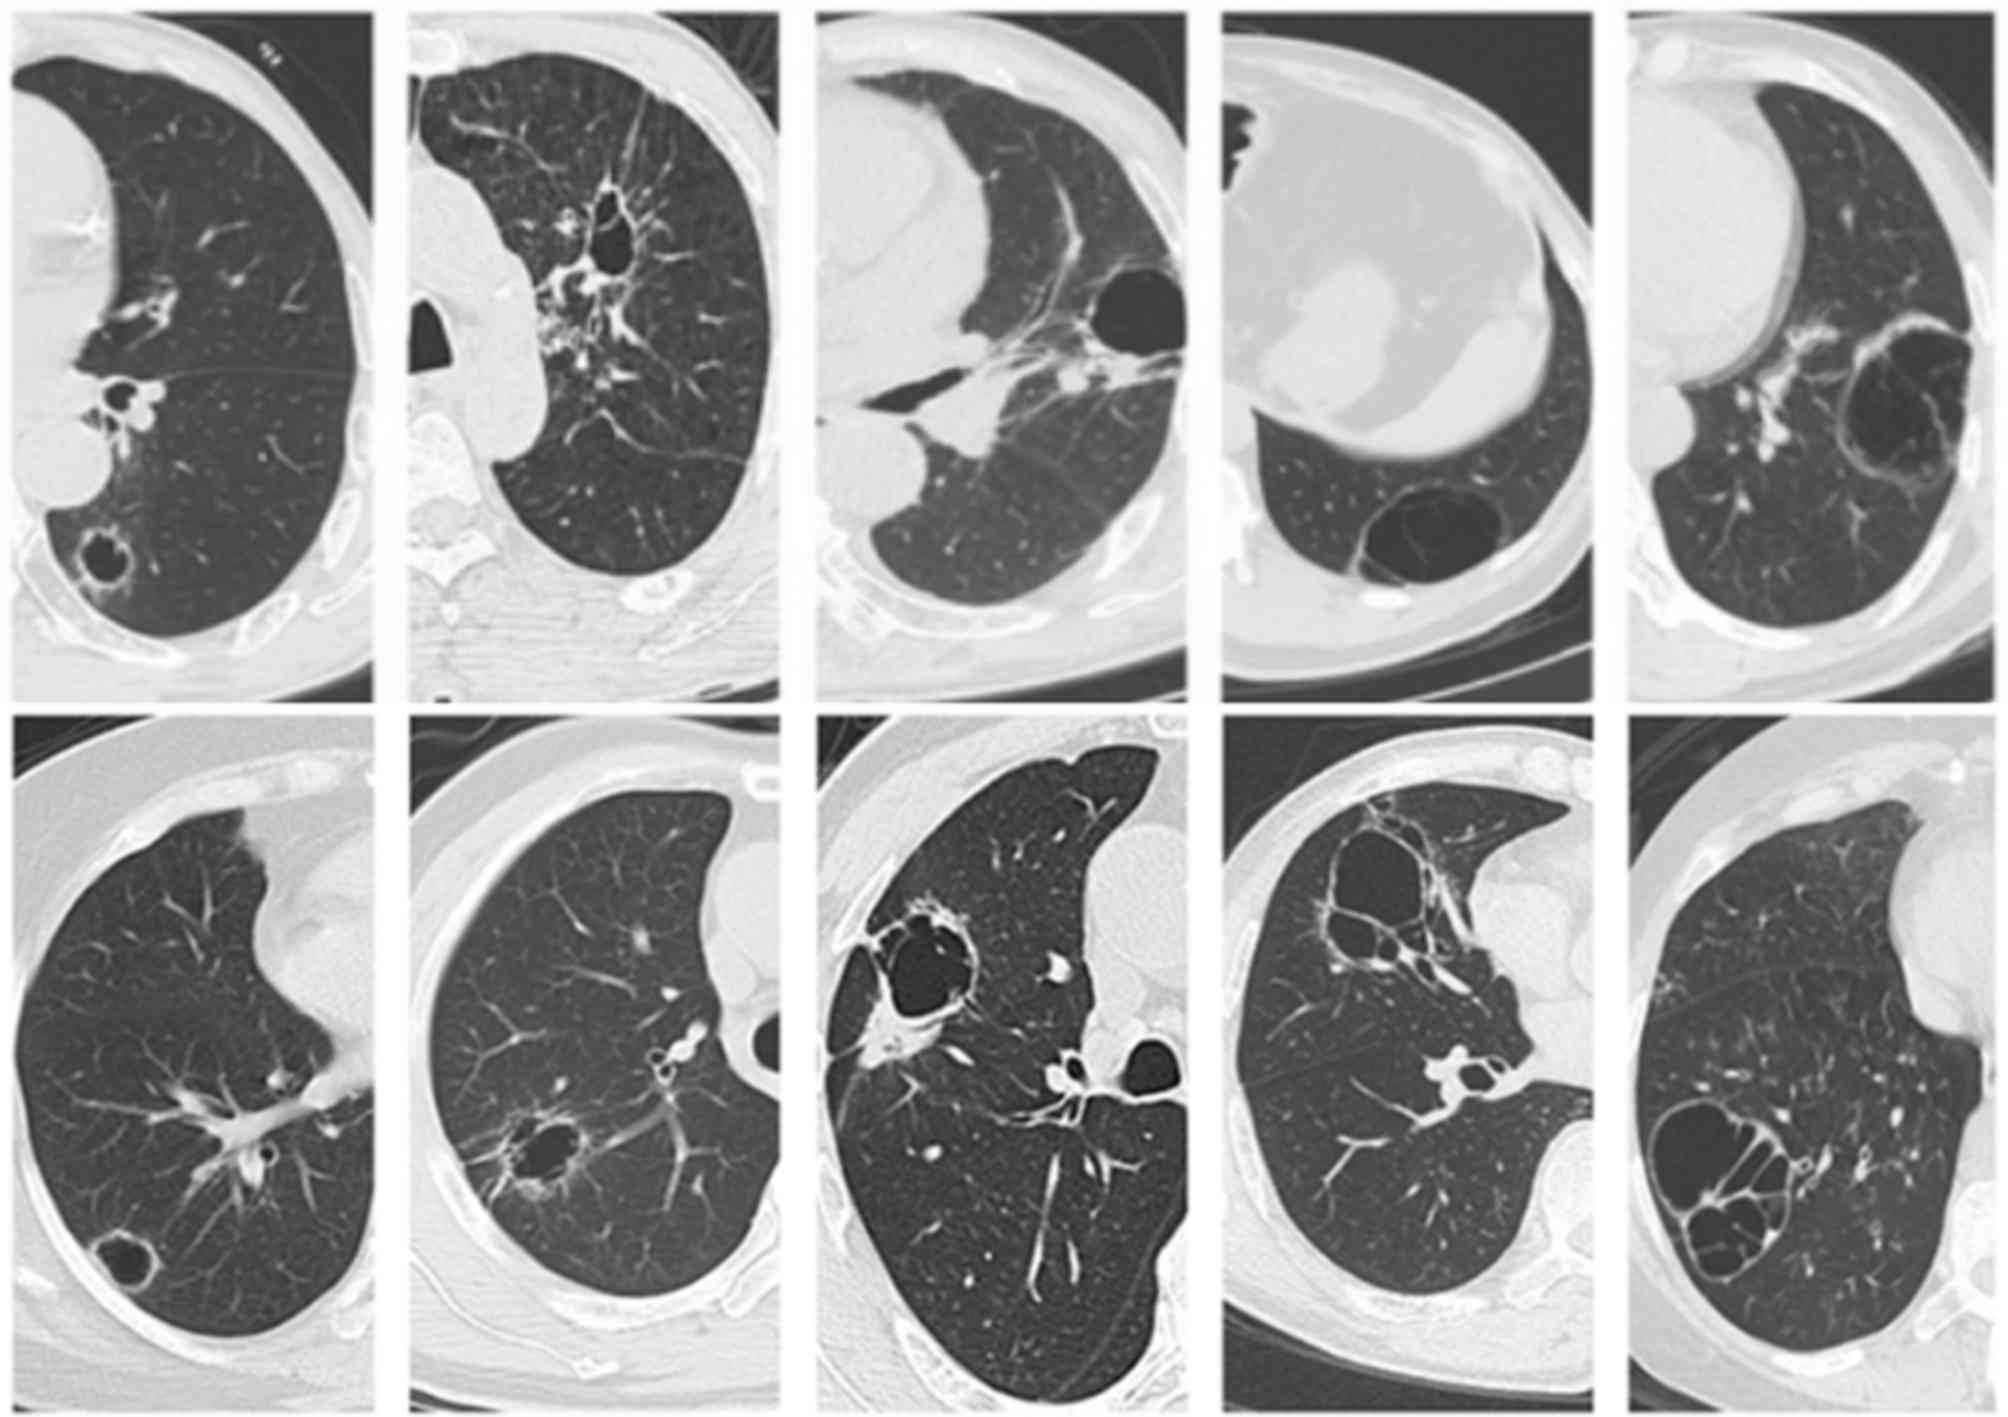

Fig. 1 demonstrates CT manifestations of thin-wall cystic lung cancer. The primary lesions occurred at the right lower lobe in 14 patients, at the right middle lobe in 5 patients, at the right upper lobe in 4 patients, at the left upper lobe in 10 patients, and at the left lower lobe in 12 patients. The wall thickness of cysts ranged between 1 and 4 mm. Each of them displayed one or more suspected malignant signs of lung cancer, including asymmetric thickening (96.8%), separation in cysts (54.8%), irregular margin (51.6%), small spicules (35.5%), dragging sensation in the pleura (22.6%), lobulation (19.3%) and ground-glass opacity (9.6%).

The pathological results confirmed the diagnosis of adenocarcinoma in the 43 patients. Two patients had squamous cell carcinoma, and also displayed cysts on the images (Fig. 6). Tumor cells (black arrow) destroyed the wall of bronchi (white arrow) (Fig. 7A). The entire cavity wall was covered with tumor cells in patients who underwent surgery. The black arrow represents area of the wall covered with tumor cells and the white arrow represents the area of the wall not covered with tumor cells (Fig. 7B). Hyperplastic fibrous tissue was observed inside the cyst (Fig. 7C). The blood vessels (indicated by the white arrow) blocked the proliferation of tumor cells (Fig. 7D).

Thin-wall cystic lung cancer is most common in adenocarcinomas. Xue et al (11) reported that thin-wall cystic lesions were detected in 15/18 patients with moderately- or well-differentiated adenocarcinoma. Qi et al (12) also reported 16 cases of adenocarcinoma. In the present study, a 57-year-old man presented with primary thin-wall cystic squamous cell carcinoma. Initially he was diagnosed with tuberculosis cysts, but a bronchoscopic biopsy identified it as poorly-differentiated squamous cell carcinoma. The lesion displayed the suspected malignant signs of lung cancer, including asymmetric thickening of the wall, short spicules, lobulation and irregular margins. However, no necrosis was observed inside the lesion. This case indicates that thin-wall cystic lesions are not limited to adenocarcinoma.

A check-valve mechanism is widely accepted (13–16). The check-valve is difficult to observe in pathological sections. Out of 45 patients in the present study, tumor cell infringed bronchiolar walls were only observed in 3 patients, which may alter bronchial structure and lead to obstruction and collapse of the trachea. We hypothesized that with air in the trachea, enclosure will be formed during expiration, forming a one-way flutter valve. The hyperplastic fibrous tissue maintains a certain tension within the cyst.